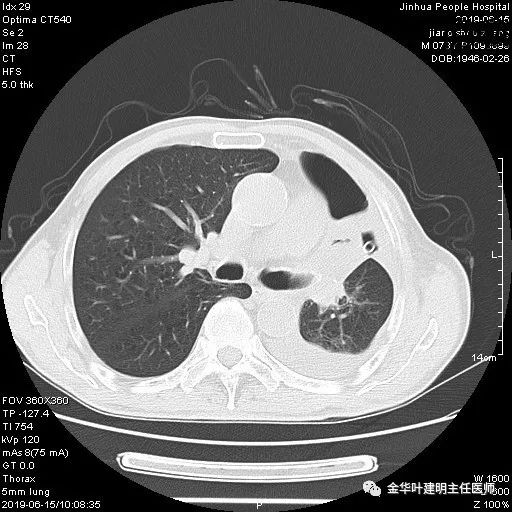

考虑左侧大量胸腔积液,遂进一步胸部CT检查:

以上是肺窗表现,下面为纵隔窗影像: